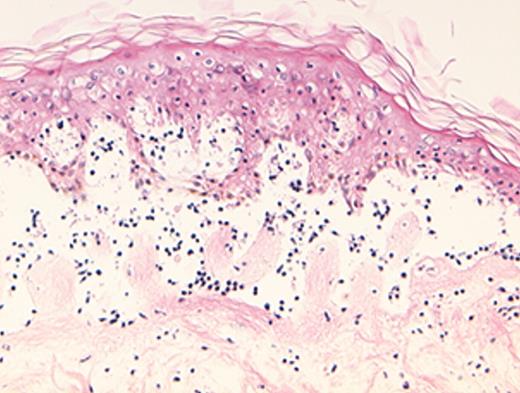

(in Barrett et al). In situ localization of mHa-specific cytotoxic T lymphocytes (CTLs) in the skin explant assay.

Skin sections of an HLAA2 male individual were incubated with autologous peripheral blood mononuclear cells (PBMCs)—data not shown, or with H-Y- or HA-1-specific CTLs.

Figure 2a. H-Y-specific CTLs showing grade IV reactions.

Figure 2b. Skin sections incubated with FITC-conjugated CD8 antibodies (green) plus APC-conjugated (red) tetrameric HLA-A2-H-Y peptide complex (H-YA2 tetramer)—analyzed by confocal microscopy

Figure 2c. Mild histopathological changes induced by HA-1-specific CTLs.

Reprinted with permission of the Nature Publishing Group (http://www.nature.com).44